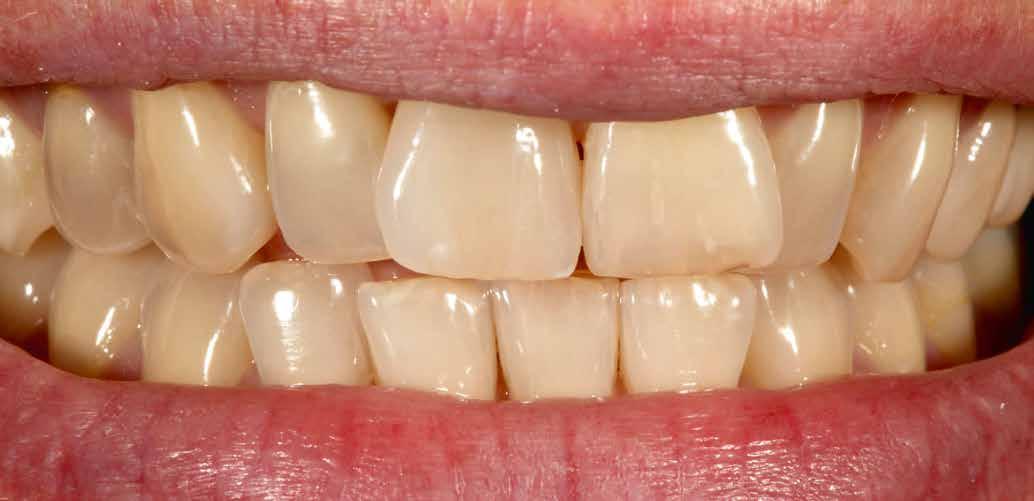

A CAD/CAM elterjedése ellenére az analóg eljárások nem szűntek meg funkcionálni. Esetbemutatásunk demonstrálja, hogyan rehabilitáltunk sikeresen az esztétikus zónában jól bevált munkamenettel, de új préskerámia recepttel. Az eredmény: természetes transzlucencia, opaleszcencia, fluoreszcencia – és egy boldog páciens.

A kiindulási helyzet recessziókkal és szabálytalan éli lefutással.

A pácienseset

Ötvenéves hölgy elégedetlen volt felső frontfogai esztétikai megjelenésével. Ezért elment a rendelőbe. Klinikailag vesztibulárisan két nagy kompozittömés volt megfigyelhető, széli elszíneződéssel. Az élek lefutása egyenetlen, aszimmetrikus volt. A frontfogakon recessziók és a nyakak szabaddá válása volt megfigyelhető. A hölgy a fogív gyors restauratív nivellálását kívánta. A nagymetszők közötti diasztémát csökkenteni kellett, de nem zárni, hogy megmaradhasson az optimális hossz-szélesség arány. A recessziók kötőszöveti fedését műtéttel kizárta. Viaszmintázat és intraorális mock-up segítségével szimuláltuk a teljes kerámiahéjakat, illetve segítettük a minimálinvazív preparációt a zománc területén. A páciens világos színű restaurációt akart. Vázanyagként a felső frontok területén a VITA AMBRIA anyagot terveztük használni, hogy a héjak életteli, színhelyes alapot kapjanak, egyidejűleg elérve az igen magas, 500 MPa-os szilárdságot. Az egyéniesítés megvalósítását VITA LUMEX AC leucit-erősítésű üvegkerámiával terveztük, hogy kevés, szín- és formastabil égetéssel reprodukálhassuk a fogakat. A 23-as szemfogat – palatinálisan megfigyelhető defektusa miatt – egyedüliként teljes koronával terveztük rehabilitálni, ugyanezzel az anyagkombinációval. A bukkális folyosó feltöltése érdekében a premolárisokra is héjak kerültek. Ezek természetes fluoreszcenciájának, transzlucenciájának és opaleszcenciájának eléréséhez monolit VITA AMBRIA munkákat készítettünk, felszíni festéssel.

Behelyezés és összefoglalás

A klinikai próba során a hölgy mégis a központi diasztéma teljes zárását kérte, amit korrektúrégetéssel valósítottunk meg. A folysavazást és szilanizálást követően a kilenc héj és a korona adhezív módon, kompozittal került rögzítésre. A régi, jól bevált analóg módszer az új VITA AMBRIA receptnek köszönhetően hatékonyan valósította meg préskerámiával az esztétikus zóna rehabilitációját. A préskerámia természetes transzlucenciája, opaleszcenciája és fluoreszcenciája élő bázist adott az egyéniesítéshez és karakterizáláshoz. A préselés utáni minimális reakciós réteg gyors kibontást és kidolgozást tett lehetővé. A préskerámia robusztussága biztonságot hozott. Az optikai összhatás és összjáték a VITA LUMEX AC leplezőkerámiával hatékonyan segítette a páciensre jellemző finomságok megjelenítését. A hölgy nagyon elégedett volt új mosolyával.